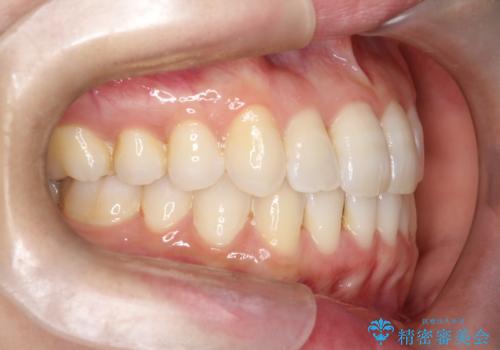

【インビザライン】前歯の凸凹をなおしたい

- 前歯の凸凹を主訴に来院されました。

上顎の急速拡大を行なったのちインビザラインにて治療を行なっております。

今回のケースは後戻りのリスクを低くし、またディスキング量を減らすために上顎の急速拡大を行なっております。